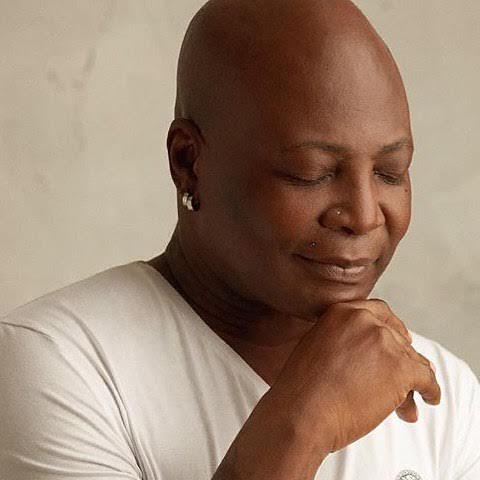

“Men-O-Pause” – Charly Boy Writes.

“If you are above 40yrs old, then you have every business reading this. If not however, you still need to go ahead and read because your own time dey come.

The stage I am at now and what am going through, is what I have discussed with so many men including my father-in-law in the past 30yrs. I never thought or even imagined I would one day be wearing the same shoes myself.

Some men right now are experiencing symptoms that include fatigue, serious mood swings, depression and wait for it….sexual problems; like not being as desirous of your spouse sexually as you have been in the past. Like noticing things you didn’t use to notice in the past in your house hold. Like being irritable and short fused or the feeling of being alone even when you’re surrounded by family.

Oyinbo people get name for am, dem dey call am Men-O-Pause.

An increasing amount of evidence points to an aging-related hormonal change in men that corresponds to the hormonal change in women known as menopause. Some call it “male menopause” which some believe is not entirely accurate but still gets the point across.

Much the same way women’s estrogen levels drop after a certain age, men’s testosterone levels decrease with age.

Testosterone is also known as androgen, and many doctors prefer the term “andropause” for this male condition or mid-life crisis, but all na the same pausing.

According to my research, testosterone decreases very gradually, in the area of 1 percent per year starting around age 35, don’t take my word for it, go ask your doctor or go read it up. So Na him be say my own don decrease by 30%? Kai!!!! See life.

Some of the symptoms are remarkably similar to those experienced by women in menopause, including moodiness, fatigue, thinking too much, depression, decreased sex drive. Hummm, my brothers, old age no fit hide sha, no matter the charlyboy in us.

My guy, this life funny o. See me, see menopause. Tufiakwa. I reject it in Jesus Name!

Na so I know reach o, Men…Ohhhh…Pause!!!”